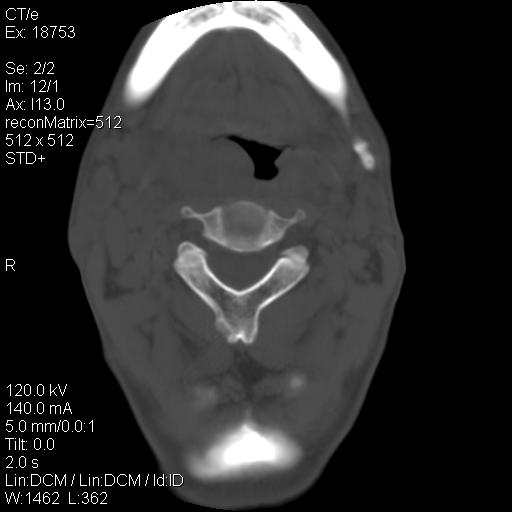

标题: CT21693:男 58岁 右侧咽部疼她2天余 PE:右侧扁桃体肿大 压痛 [打印本页]

标题: CT21693:男 58岁 右侧咽部疼她2天余 PE:右侧扁桃体肿大 压痛

1 弥漫性肿胀,与周围组织分界清晰,发病急,有明显症状,考虑急性炎症【wbc]

弥漫性肿胀,与周围组织分界不清,发病急,有明显症状,考虑:感染性病变!

右化脓性扁桃体炎症伴咽后壁脓肿形成.